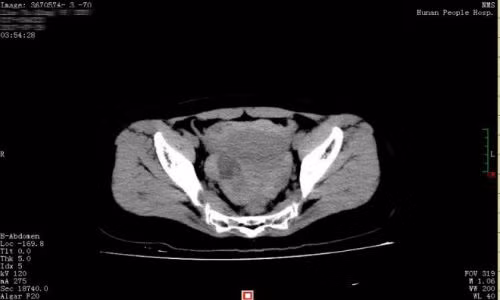

Bác sĩ Huang Mei thuộc Bệnh viện Nhân dân tỉnh Hồ Nam (Trung Quốc) cho biết Hiểu Khánh không mang thai, bản chụp CT phát hiện ra cô có một lượng máu lớn và chất lỏng trong ổ bụng và vùng chậu.

Sau khi thực hiện phẫu thuật nội soi ổ bụng, họ nhận thấy máu xuất hiện trong khoang phúc mạc của Hiểu Khánh, tìm thấy một u nang buồng trứng phải đã bị vỡ. Ngay lập tức cô được đưa đi phẫu thuật loại bỏ u nang.

“Khoảng 1.500 ml máu đã mất đi, chiếm tới 40% lượng máu của cơ thể cô gái này. Nếu chỉ đưa vào chậm hơn, cô ấy có thể gặp nguy hiểm đến tính mạng”, bác sĩ Huang nói. Hiện Hiểu Khánh đã qua cơn nguy kịch và được điều trị ở bệnh viện tỉnh Hồ Nam.